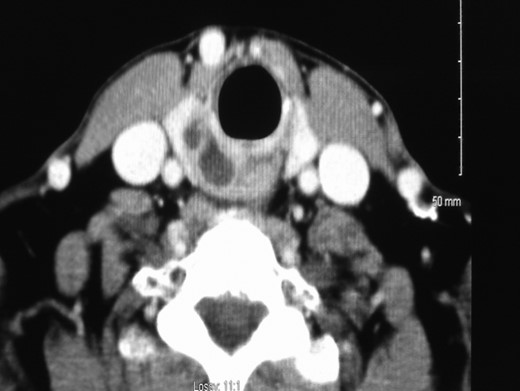

Physical examination revealed no evidence of disease within the oral cavity or cervical lymphadenopathy. Nasoendoscopic evaluation of the larynx revealed a complete right vocal cord palsy but no obstructing airway lesion was identified. Contrast enhanced computed tomography (CT) of the neck revealed a bi-lobed cystic mass (2.0 × 1.3 cm2) medial to the inferior lobe of the right thyroid associated with the cricoid cartilage causing displacement of the oesophagus (Fig. 1).

Contrast enhanced computed tomography of the neck showing a bi-lobed cystic mass (2.0 × 1.3 cm2) medial to the inferior right lobe of right thyroid associated with the cricoid cartilage causing displacement of the oesophagus.